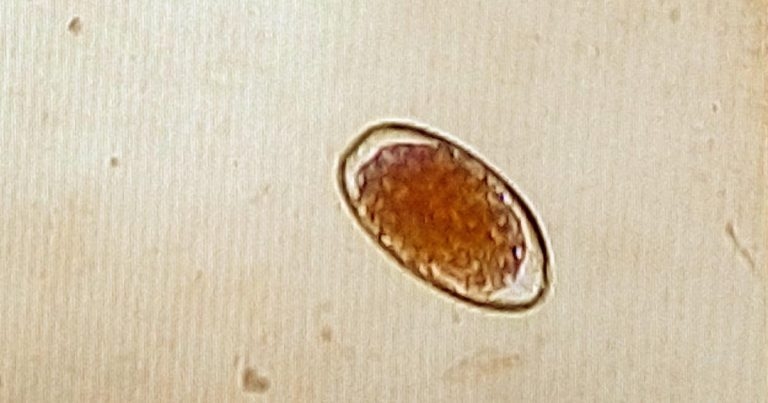

Figure 1. An egg (~85µm × 45µm) of abomasal nematode recovered from the faeces of cattle using the McMaster method.

Anthelmintics belonging to these chemical groups are active against the major species of GI roundworms and lungworms, with some also having activity against liver flukes. Macrocyclic lactones have activity against endoparasites and some ectoparasites, and are often referred to as endectocides. Other products, known as narrow spectrum drugs, are more specific in the parasites they kill, but are also active against certain ectoparasite species. Therefore, anthelmintic drugs should be chosen to target the species of worm (whether adult or juvenile form) highly likely to be involved in the infection, or that has already been identified using laboratory diagnostic methods, such as faecal worm egg count (Figure 1).